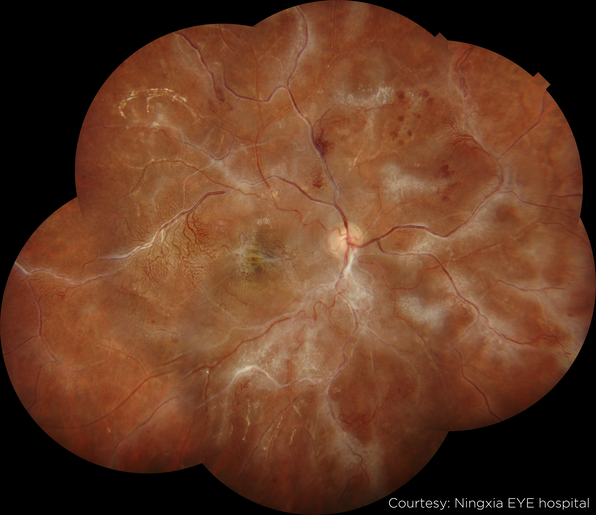

Image Gallery